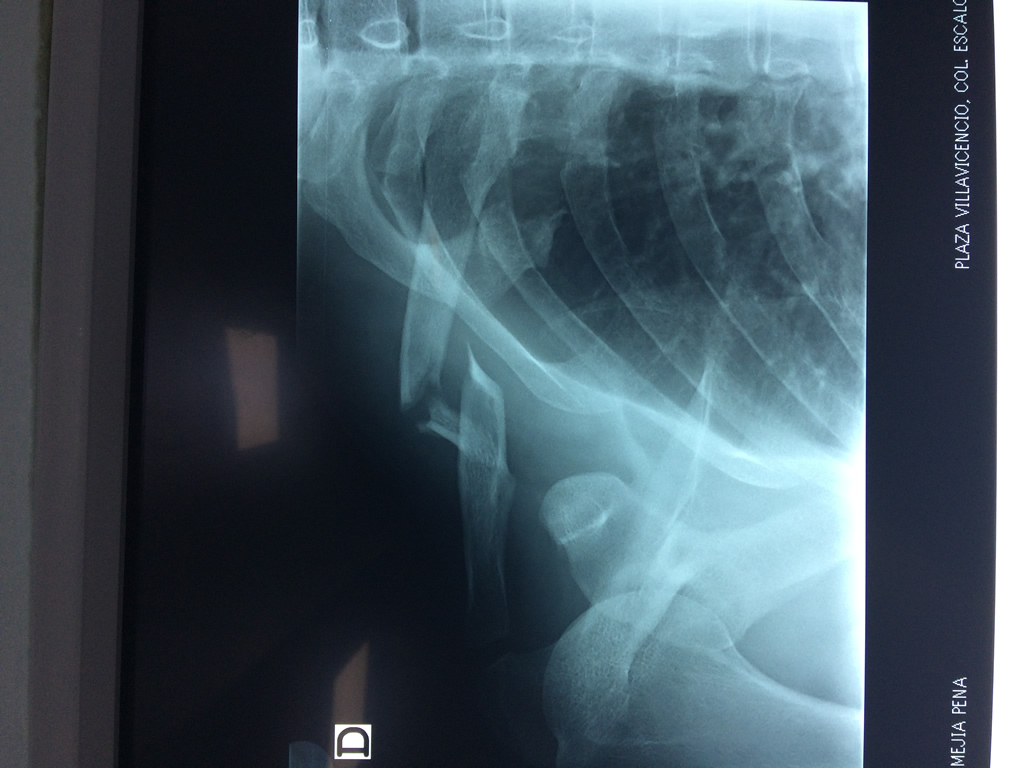

La clavícula es un hueso largo, con forma de "S" itálica, situado en la parte anterosuperior del tórax. Junto con la escápula forman la cintura escapular. Se puede palpar por toda su longitud y se extiende del esternón al acromion de la escápula, siguiendo una dirección oblicua lateral y posterior.

Se considera el único medio de unión entre el miembro superior y el tórax. A pesar de su aspecto, similar al de un hueso largo, posee una estructura semejante a la de un hueso plano, ya que carece de epífisis y de diáfisis, lo que la harían entrar dentro de la clasificación de hueso largo. Carece de un canal medular propiamente dicho.